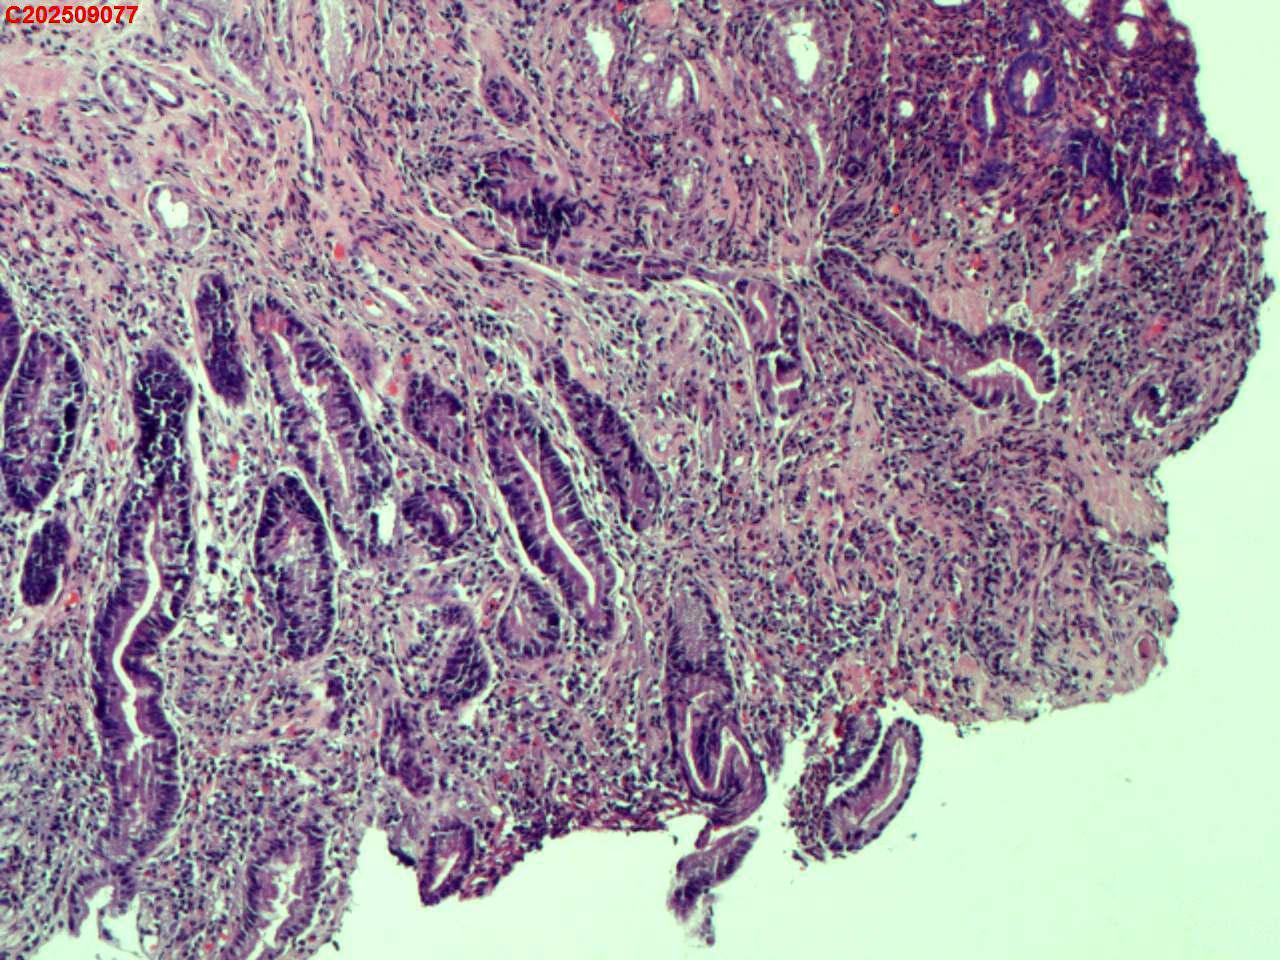

胃角粘膜

性别

男

年龄

65岁

临床诊断

胃炎伴糜烂

一般病史

体检

标本名称

大体所见

胃角多发片状充血、糜烂

图2

萎缩+肠化+修复。